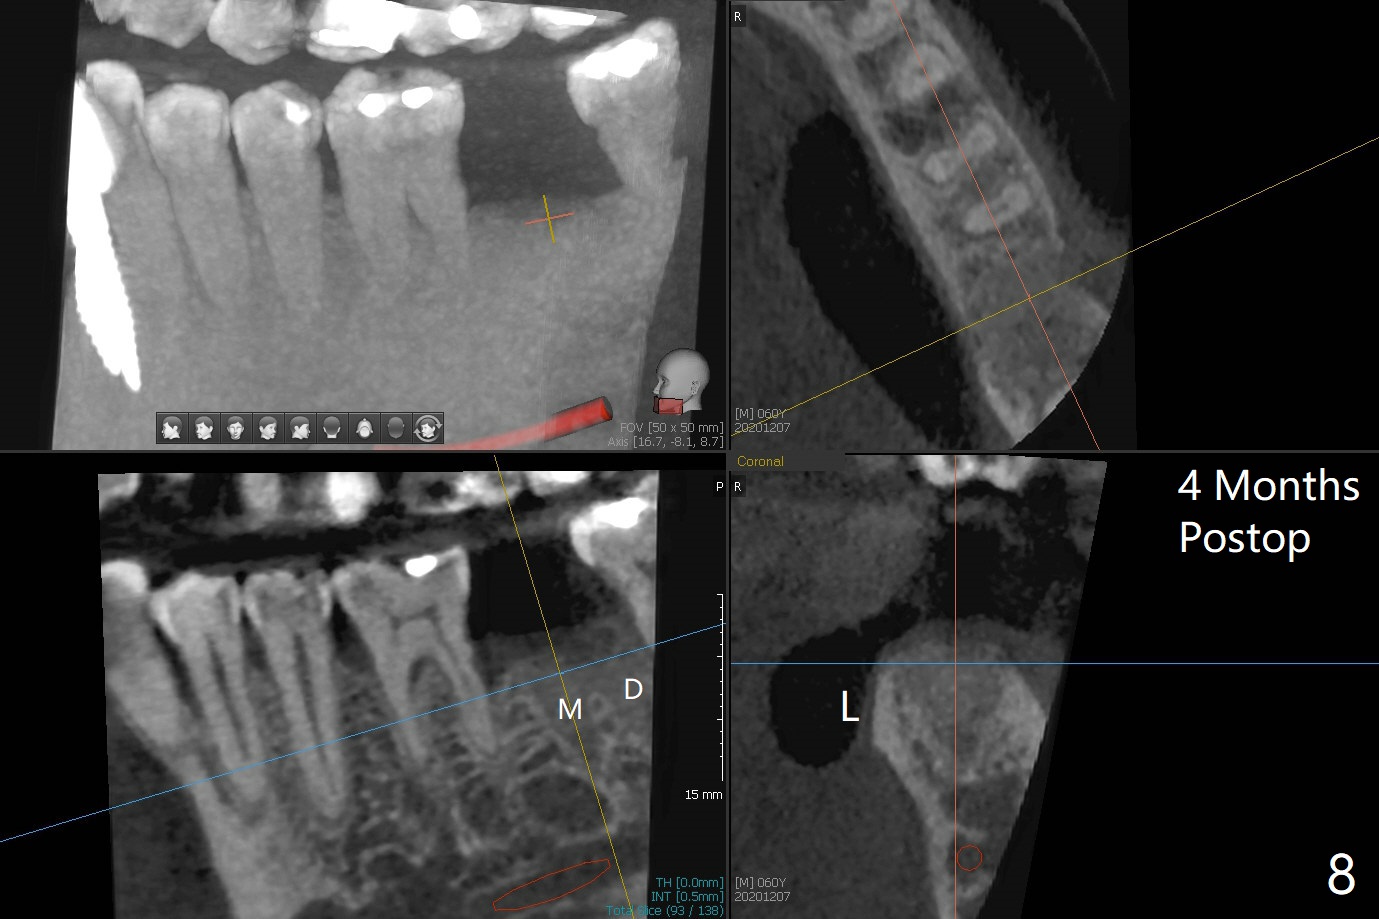

60岁男,吸烟,口腔卫生不好,不积极配合治疗,下前牙两个植体螺纹暴露,但是没有症状。两年中,左下七(图一,二)不能保留(图三),虽然六远中结石被清除(图三>),七位点保留(图四 *)时未能顺便在六远中填入骨粉(用血混合,胎盘膜覆盖)。四五个月后,七种植时将钻头骨粉放置于六远中缺损处,如何才能让骨粉在患处生根发芽?术后一个月,去除树脂敷料后,最表面骨粉未能被整合,下面骨粉好像已经与肉芽组织结合了(图五),其实根尖片应该拍摄证实这一点。吸烟者血供不好,愈合欠佳。术后三个月牙槽嵴宽(图六);高度稍微减低(图七)。术后4个月CT显示近中牙槽窝正好位于缺牙区正中(图八),所以植体必然进入近中窝(图九)。

完成钻洞后(图十),潜行分离(掀开)近中牙龈(图十一),去除6远中肉芽组织和结石(图十二),涂Endogain,放置粘性骨粉(图十三),最后放置植体。